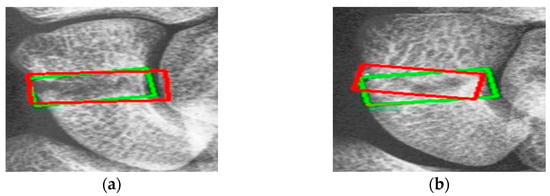

Figure 9 shows the results of scaphoid fracture detection. In the figure, the red area represents the ground-truth box labeled by the doctor, while the green area shows the result predicted by the model. Figure 10 provides an example of a more obvious fracture, whereas Figure 11 illustrates an example of an occult fracture. These examples highlight the challenges in diagnosing scaphoid fractures, as occult fractures are difficult to distinguish by the naked eye. The AP views demonstrate a relatively high IoU, while the LA views also accurately locate the fracture area. This combined approach is effective in drawing the doctor’s attention to the area, enabling quicker identification of the fracture location.

Figure 9.

Scaphoid detection visualization. (a–d) The AP and LA views of the same patient. The first row is the ground truth, and the second row is the predicted result.

Figure 11.

Occult fracture detection visualization. (a,b) Scaphoid bone slices. The red box is the true answer, and the green box is the predicted result.